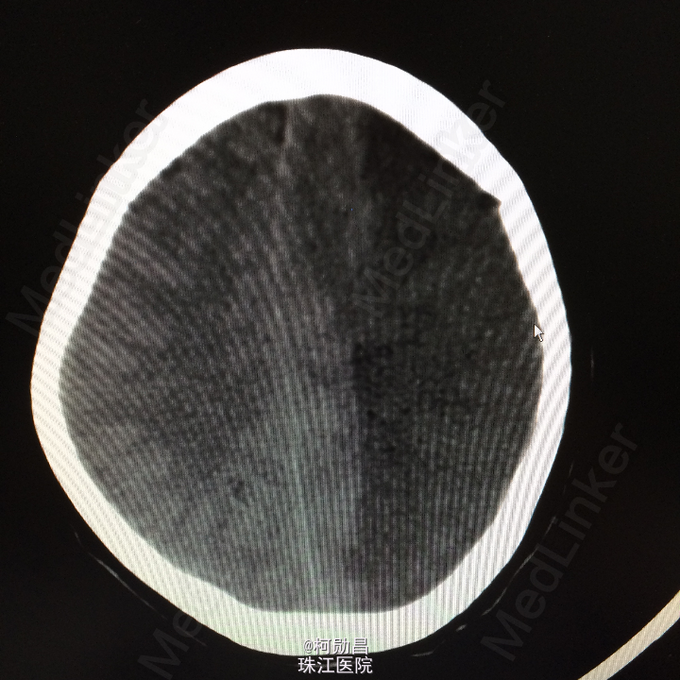

主诉:突发言语不能伴右侧肢体无力1天余 病史:患者于1天前无明显诱因突发言语不能,伴右侧肢体无力,表现为右侧肢体不能自主活动,无头痛头晕,无恶心呕吐,无肢体麻木、四肢抽搐、意识不清等症状。于当地医院就诊,查头颅CT提示:未见异常,予对症支持治疗,症状无好转。半天前患者症状加重,出现神志不清,呈嗜睡状态,现患者为求进一步诊治,遂至我院。门诊拟以“大面积脑梗塞”收入院。

查体:神志呈昏睡状态,言语不能,精神差,双侧瞳孔不等大,左侧3mm,对光反射消失;右侧瞳孔2,mm,对光反射灵敏,右侧肢体肌力0级,左侧肢体肌力5级,右侧肢体肌张力减低,余未见异常。 辅助检查:左侧大脑半球累计岛叶、基底节区(以颞顶叶为主)大片状低密度影,考虑脑梗塞;中线结构明显右移。

诊断:大面积脑梗 处理:予对症支持治疗,运用抗血小板治疗,抗凝治疗